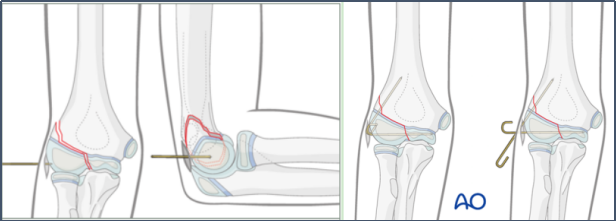

手术治疗-闭合复位内固定

闭合复位经皮固定:适用于2-4mm移位,全麻下通过屈肘、前臂旋前、外髁直接加压复位,用1.6mm克氏针固定,理想为2-3根成角>60°的克氏针,实现双皮质固定,残留移位需<2mm。

适应症选择:适用于骨折移位>2mm,但关节面软骨铰链完整或无明显旋转的骨折(如Weiss II型、Song II-IV型)。

手术核心技巧:

复位:手法或细针撬拨,将移位骨块推回原位。

固定:经皮穿入2-3根克氏针,优选交叉固定以增强稳定性。

图16 使用克氏针作为杠杆以辅助复位,然后继续推进至肱骨小头,并交叉固定骨折断端。

确认:术中反复透视或关节造影,确保关节面解剖复位。

图17 关节造影证实关节面平整。